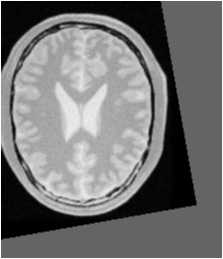

我们得到的图像相比如原来的来说:

平移变大 原有图像

这个时候我们得到的图像相对于原来的来说,朝着左上角平移了一定距离。

所以上面猜想是正确的。